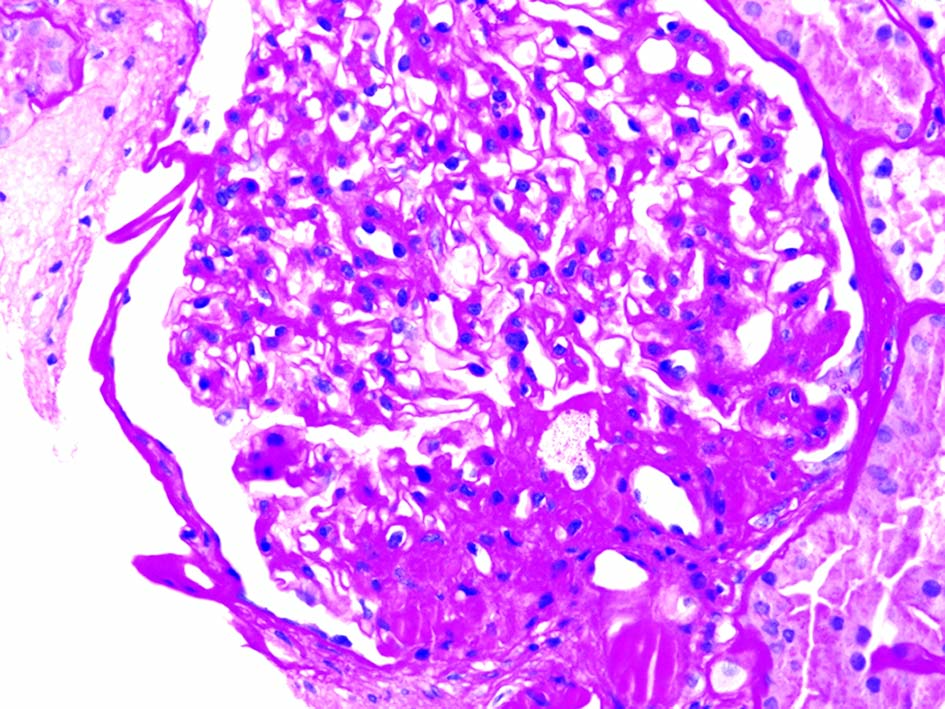

These various effects result in specific pathologic changes in the kidneys [41] which could underlie the higher risk of CKD seen in observational studies. These include ectopic lipid accumulation [42] and increased deposition of renal sinus fat [43, 44], the development of glomerular hypertension and increased glomerular permeability caused by hyperfiltration-related glomerular filtration barrier injury [45], and ultimately the development of glomerulomegaly [46], and focal or segmental glomerulosclerosis [41] (Fig. 2). The incidence of the so-called obesity-related glomerulopathy (ORG) has increased 10-fold between 1986 and 2000 [41]. Importantly, ORG often presents along with pathophysiologic processes related to other conditions or advanced age, conspiring to result in more accentuated kidney damage in patients with high blood pressure [47] or in the elderly [14, 39].

![]() Click for large image | Figure 2. Obesity-related perihilar focal segmental glomerulosclerosis on a background of glomerulomegaly (periodic acid-Schiff stain, original magnification, × 400). Courtesy of Dr. Patrick D. Walker, MD; Arkana Laboratories, Little Rock, AR. |